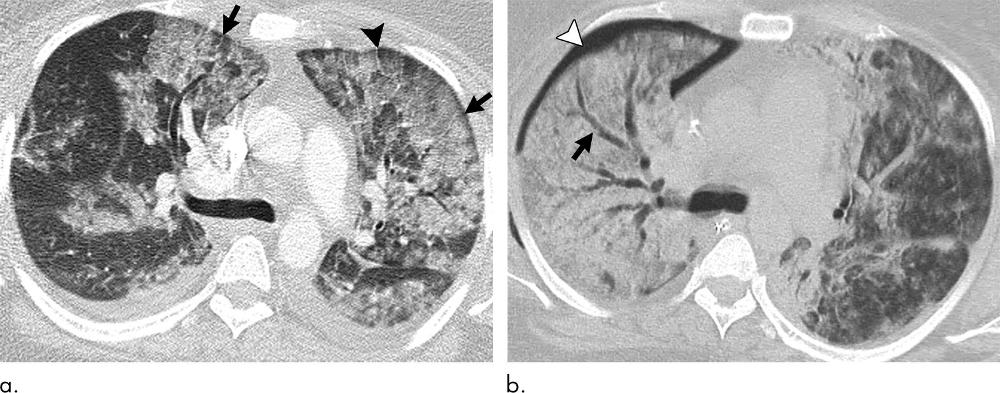

Figure 4. Images show electronic cigarette or vaping product use–associated lung injury with organizing pneumonia pattern in an 18-year-old man who vaped nicotine and tetrahydrocannabinol with fever of 103°F, vomiting for 3 days, and negative workup for infection and rheumatologic disease. (a) Posteroanterior radiograph shows perihilar predominant hazy opacity with conspicuous sparing of both heart border (white arrows) and periphery (black arrows). Septal thickening is present (arrowhead). (b) Corresponding CT image shows perihilar predominant ground-glass opacity with prominent sparing of subpleural interstitium both peripherally and centrally (black arrows) with intermixed areas of lobular sparing. In addition, there is sparing of peribronchovascular interstitium (white arrows). Septal thickening (black arrowhead) and scattered centrilobular nodules are present (white arrowhead). Patient rapidly improved after administration of steroids.